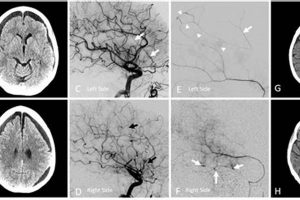

MMA, in the context of interventional radiology, stands for middle meningeal artery. Embolization is a minimally invasive procedure used to block blood flow to a specific area. Thus, middle meningeal artery embolization... Read more »

This minimally invasive procedure addresses a specific type of brain bleed, a subdural hematoma, by targeting the source of the bleeding within the meningeal arteries. A specialized catheter is navigated through the... Read more »

This minimally invasive procedure involves blocking blood flow to the middle meningeal arteries, typically on both sides of the head. It is often performed by interventional neuroradiologists using specialized catheters and embolic... Read more »